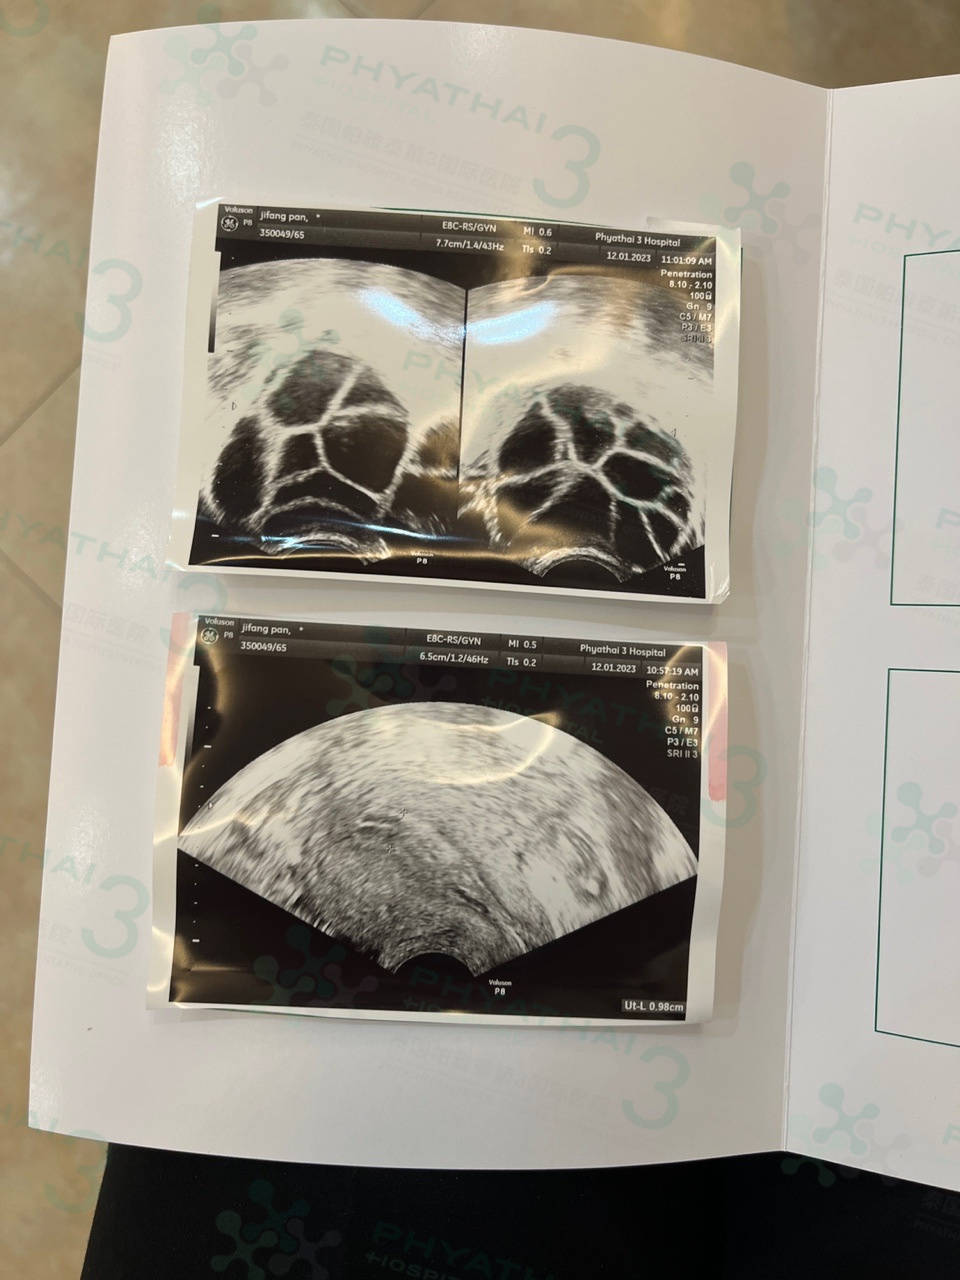

泰国试管要取卵啦~今天是第三次见诊了,患者卵泡对药吸收的不错 今天卵泡达标可以取卵了, 库医生还强调患者要多喝水多吃鸡蛋白缓解缓解腹胀 注意事项都跟患者说了 医生估计14毫米以上的可以取但是取卵当天医生也会每一个卵泡里面的卵子都取出来 而且还会关注生理盐水看看子宫内膜情况是否有息肉、肌瘤、粘连等 今晚就打夜针了 后天取卵啦 希望能取到多质量好的卵子